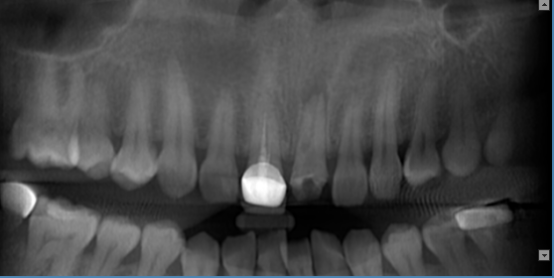

种植:

1.提供各种颌面信息及三维图像信息,精确地获得所需术前诊断信息。

2.为种植提供测量颌骨宽度、长度、密度及各种距离、角度等综合信息,以选择各种种植体尺寸及位置。

3.重要结构的定位,种植体间距离安全碰撞检测(神经管、上颌窦、病变位置等)避免手术中发生突发情况。

4.真实模拟种植体的位置,可选择任意种植型号、大小尺寸等,方便医患直观交流讨论。

5.定制手术外科导板,精确定位种植体位置及方向,提供微创及即刻种植方案